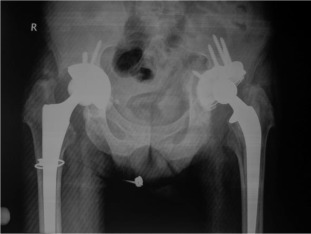

There were 61 patients (50 male, 11 female) with 105 affected hips (72% bilateral, 28% unilateral). The average patient age at surgery was 41.3 ± 10.2 years old. The age of patients at THA was as follows: <30 years for 14 patients (23 hips), 31–50 years for 41 patients (73 hips) and >50 years for 6 patients (9 hips) (Graph 1 ). The younger age at diagnosis (<30 years old) of AS was correlated with younger age at THA (p < 0.05). Bone ankylosis was detected in 37 (35%) and acetabular protrusion was noticed in 18 (17%) hips in pre-operative radiographs (Fig. 1 , Fig. 2 , Fig. 3 ; Fig. 4 ) (Table 1 ). The mean pre-operative flexion contracture was 20.3°±21.8°. In patients without ankylosis, the mean total hip range of motion (ROM) was 67.8°±25.7°.

Fig. 1. Pre-operative x-ray of a patient with bony ankylosis. |